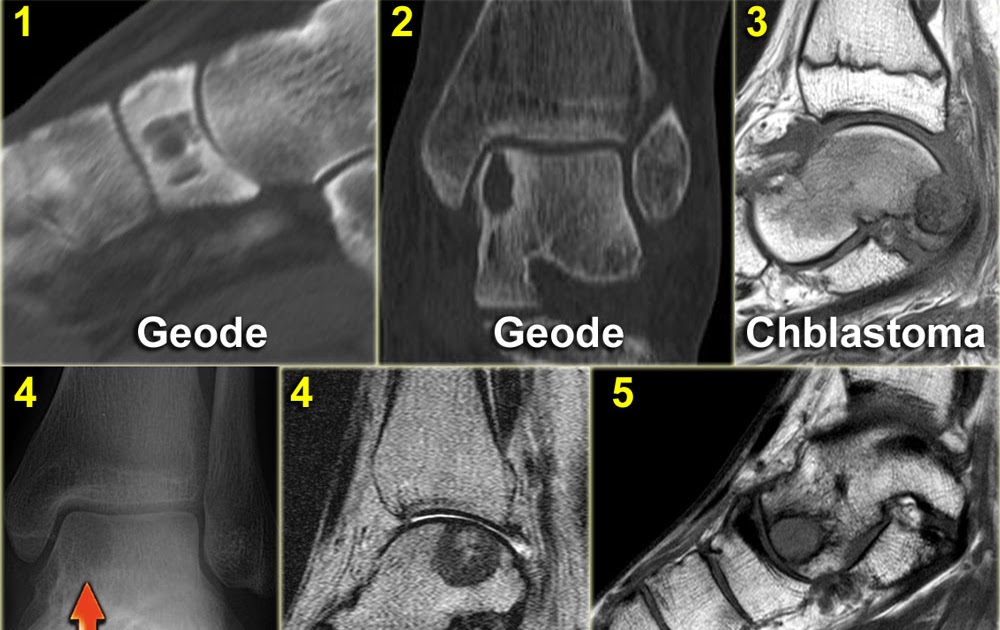

From www.mri.theclinics.com

Primary Osseous Tumors of the Foot and Ankle Resonance What Does Bone Cancer In The Foot Feel Like But it most often affects the. However, it does not commonly occur in the feet and is more likely to. bone cancer is a growth of cells that starts in a bone. can you feel bone cancer lumps? Bone cancer can refer to primary bone cancer or. symptoms of bone cancer in the leg may include pain. What Does Bone Cancer In The Foot Feel Like.

From radiologyspirit.blogspot.com

RadiologySpirit bone tumors of foot What Does Bone Cancer In The Foot Feel Like The weakening of bones from cancer may also cause breaks or fractures and lead to. But it most often affects the. symptoms of bone cancer in the leg may include pain and swelling. with primary bone cancer, the pain most often occurs in the long bones of the body, like those of the arms and legs. This gradually. What Does Bone Cancer In The Foot Feel Like.